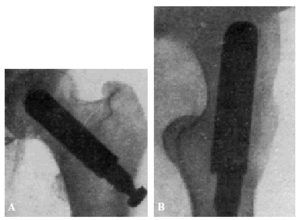

Fracaso número 4(observación número 21). Josefa T., setenta años. Afecta de síntomas de reblandecimiento cerebral. Dos meses antes de producirse la fractura, en un intervalo de quince días, tuvimos que extraerle por dos veces una cánula de lavativa de su ampolla rectal. La fractura fue tratada con el clavo de Sven Johansson (fig. 6. A y B), según la técnica habitual. A los veinte días de la intervención tuvo que pasar a su domicilio ante las quejas de los enfermos de las habitaciones próximas. La enferma estaba en una agitación constante y se quejaba continuamente. En su domicilio, donde la vigilancia no era tan severa como la de la clínica, abandonaba el lecho con frecuencia. Al mes y medio de la intervención notaron los familiares que la enferma, a pesar de su agitación, permanecía siempre en el lecho. Explorada entonces por nosotros, después de haber transcurrido una semana sin haberla visitado, comprobamos que el clavo hacía una prominencia bajo la piel, que estaba a punto de ser perforada.

Figura 6. A: obs. núm. 21. Radiografía practicada antes de la penetración completa del clavo, que en esta proyección está situado algo cranealmente. B: obs. núm. 21. Radiografía practicada antes de la penetración completa del clavo. La situación de éste es buena; con relación a la cabeza, es ligeramente ventral, debido a que la fractura no ha sido perfectamente reducida.

A pesar de que la situación del clavo no era ideal en este caso, no hay duda de que el resultado desfavorable obtenido fue condicionado por el estado mental de la enferma, la cual, o no hubiera tenido que ser operada, o, en todo caso, sometida, en el curso postoperatorio a una vigilancia más estricta.